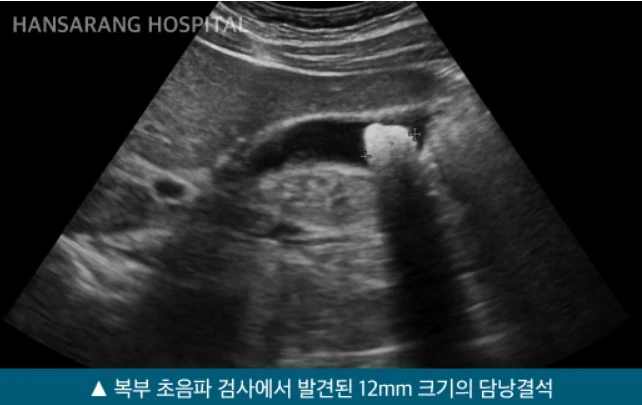

담석증(담낭결석)

흔히 담낭에 들어 있는 돌을 담석이라고 합니다. 담낭에는 간에서 만들어진 소화액인 담즙이 저장되어 있는데, 이 담즙이 굳어져서 돌로 만들어진 것을 담석이라고 합니다.

6.JPG 한사랑병원 복부 초음파를 통해 발견된 담낭 결석

담석은 담낭뿐만 아니라 담관이나 간 안의 담도에도 생길 수 있습니다. 그 종류도 다양해 담낭 담석, 간내 담석, 수담관 담석, 담낭관 담석, 총담관 담석, 유두괄약근 입구를 막은 담석 등이 있습니다. 특히, 담석의 60~80%는 증상이 없기 때문에 건강검진 시 담낭 검사에서 우연히 발견되는 경우가 많습니다.